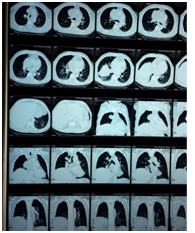

Clinical case

Male 55 years of age, genetic burden to you, dm, heart disease. Tab up to 6 months 5 cigarettes a day for 15 años. PA Starts 4 months myalgia and arthralgia, headache with decubitus, dizziness, dry cough without predominance of time, wheezy, hyperoxia, tired, exhausted, insomnia, lateropulsion, dorsalgia .disfonía ago , dyspnea small efforts, night sweats, back pain, facial edema, lower limb, abominal, upper limb and neck EFTA 90/60, FC 120X MIN, facial edema and neck, even sitting jugular plethora, thoracic venous network, adenomegalia bilateral neck and underarm, edema and abdominal wall members inferiores (Figure 1). He underwent chest CT lung tumor reporting based region right evil-looking, mediastinal tumor with calcifications and data invasion of pericardium and conditioning svcs superior vena cava, mediastinal lymphadenopathy of bilateral hilar groups prevascular (Figure 2) (Figure 3).

Figure 2 Report of CT lung tumor.

Figure 3 Report of CT lung tumor.